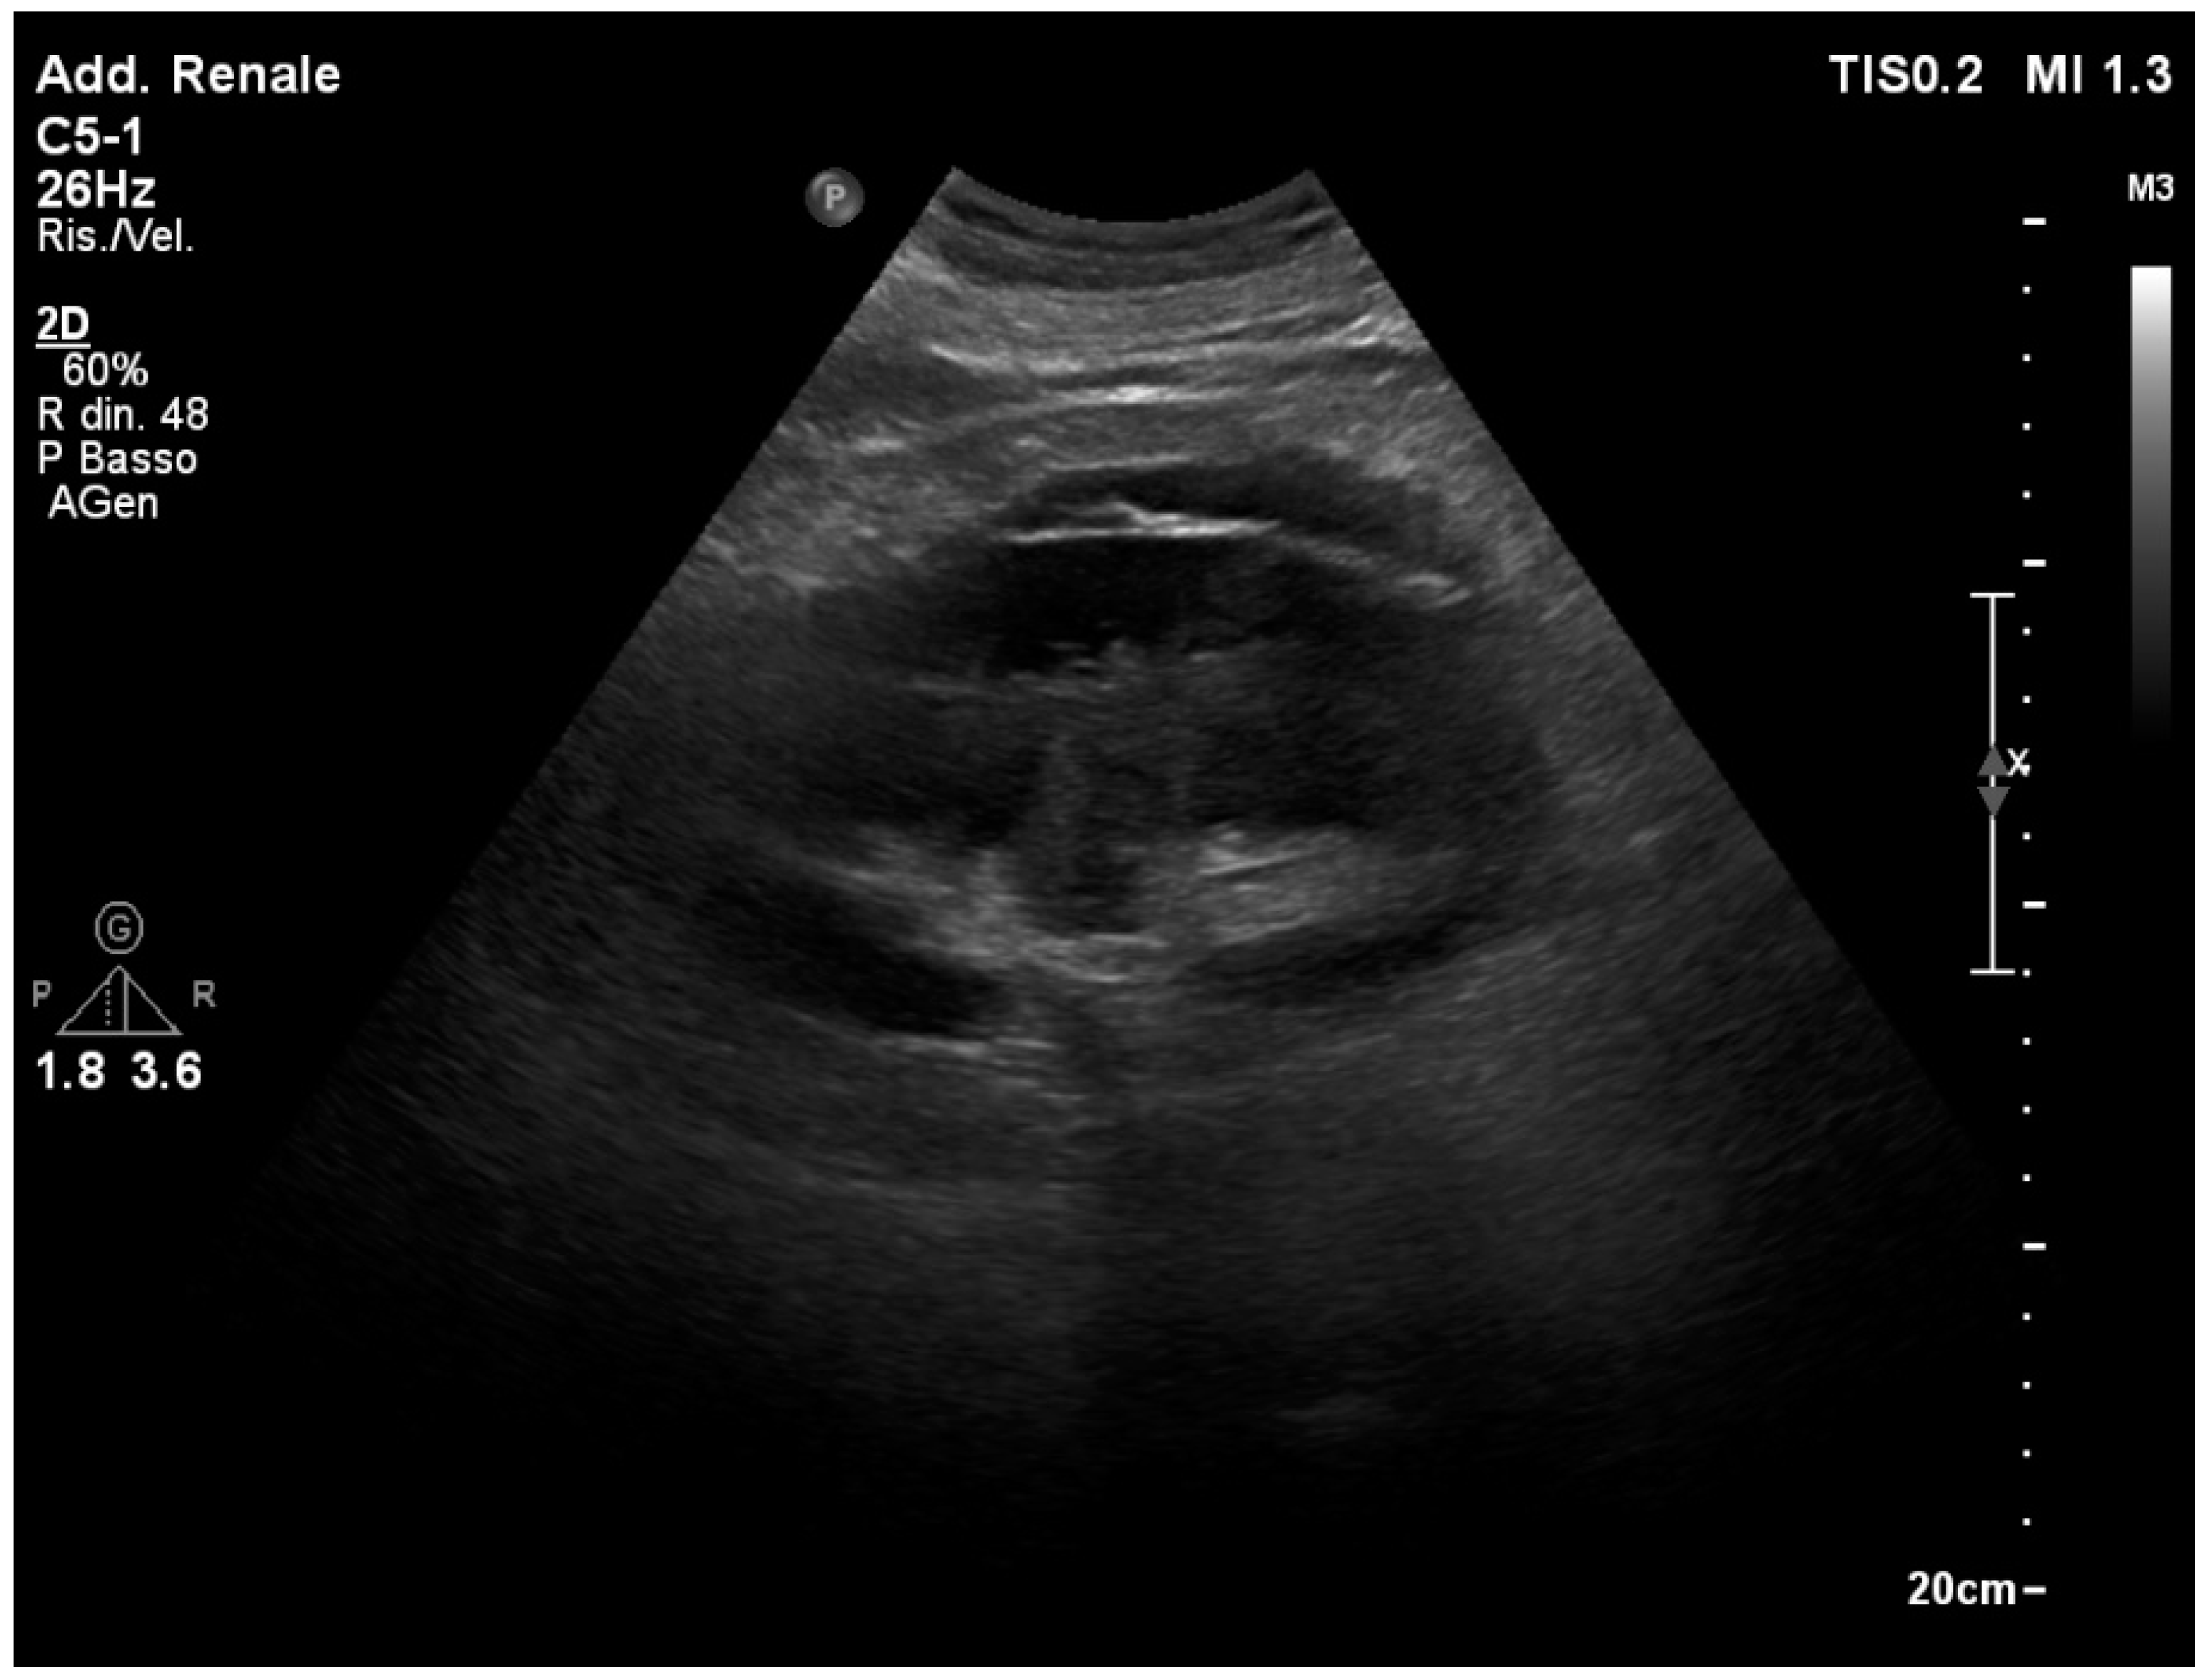

ccr31934-toc-0001-m.jpg?trick=。Frontiers | Urinary Ultrasound and Other Imaging for。Ultrasound of the Urinary System | SpringerLink。【書籍の概要】本書は腎臓超音波検査に特化した図版集であり、医療従事者や学生にとって貴重な参考資料です。視覚的な情報が豊富で、腎臓の解剖や病理を理解するのに役立ちます。【内容の特徴】各章には腎臓に関する詳細な超音波画像とともに、解説が付されています。これにより、実際の診断や研究に役立つ情報が得られます。【対象読者】医療従事者、特に放射線技師や腎臓専門医、または腎臓に関心のある学生に最適です。- 書名: ATLAS OF Renal Ultrasonography- 著者: O'NEILL- 内容: 腎臓超音波検査に関する図版と解説- 表紙の色: 青と赤のグラデーションご覧いただきありがとうございます。。。【 新品未使用 】 最新医学大辞典。宇宙論と神。DVD>松本岐子先生 明日からの臨床に使える鍼灸療法 1巻2巻set。専用⭐︎美品】健康管理士一般指導員 検定書セット 1-6巻。未開封品 DVD 岩橋 亮平 4回リピート制! 産後ママに評判の骨盤矯正